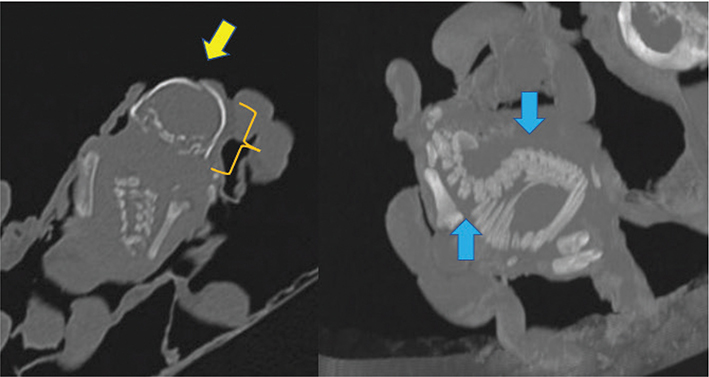

Figure 6.

Figure 6. Transverse computed tomographic image (bone window) of the skull of the smallest fetus (left) and sagittal maximum intensity projection of the same fetus’s vertebral column (right). There is a small step defect between the developing parietal bones (yellow arrow) and dorso-ventral collapse of the cranium (yellow bracket). There is moderate lordosis of the lumbar spine and kyphosis of the thoracic spine (blue arrows). These changes coupled with its smaller size may indicate earlier demise of this fetus.